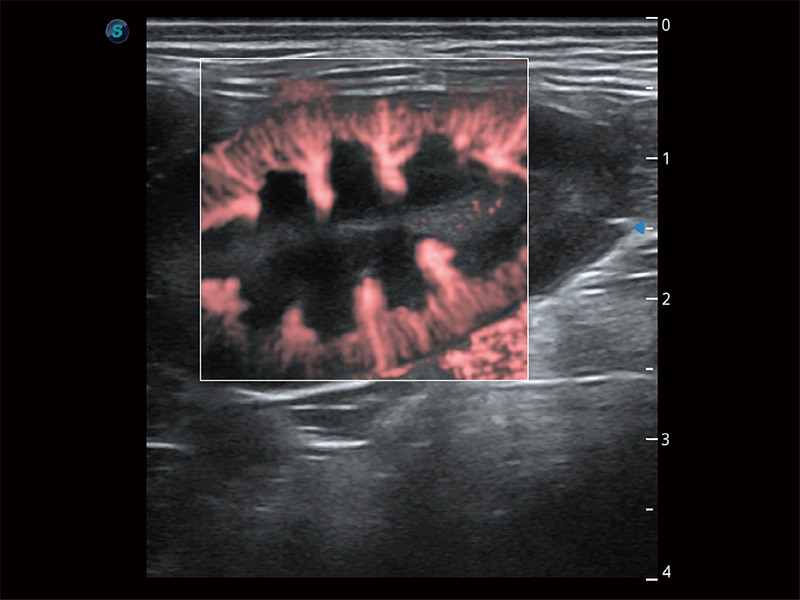

極大提升超低速微細血流的檢出能力,同時更精準地濾除軟組織和超聲信號,為獸用醫(yī)生提供以往無法通過常規(guī)血流獲得的疾病診斷信息。

在傳統(tǒng)二維血流成像的基礎上,呈現(xiàn)血流的立體感,具有動感的生命力之美。即便是微小的血管也能輕松應對,提高了血流的視覺敏感性。